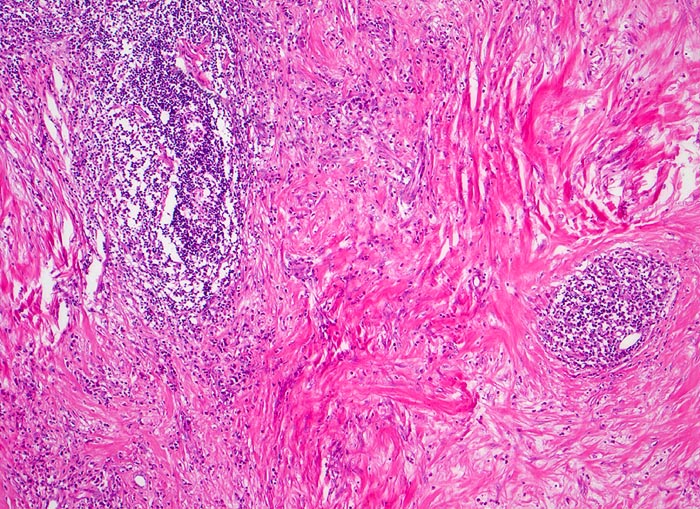

Morphologische Merkmale:

• Zerstörung der Lymphknotenarchitektur.

• Von breiten Bindegewebssträngen abgegrenzte Knoten.

• Die Knoten bestehen vorwiegend aus einem Mischzellinfiltrat reaktiver Zellen: Lymphozyten, Histiozyten, eosinophile Granulozyten und Plasmazellen.

• Reed-Sternbergzelle mit spiegelbildlich angeordneten Kernen mit sehr grossen eosinophilen Nukleolen.

• Einkernige Hodgkinzelle mit prominentem Nukleolus umgeben von einem Retraktionsartefakt (Lakunarzelle).